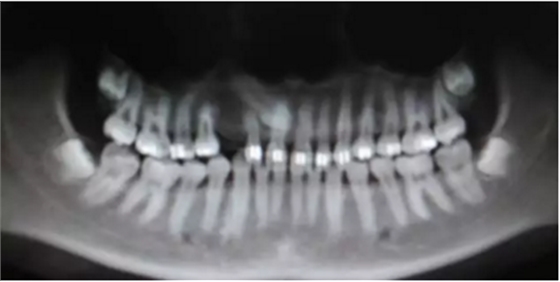

再看看逆襲的尖牙阻生。。。

小泥鰍

橫位

錯(cuò)位

大尺度異位